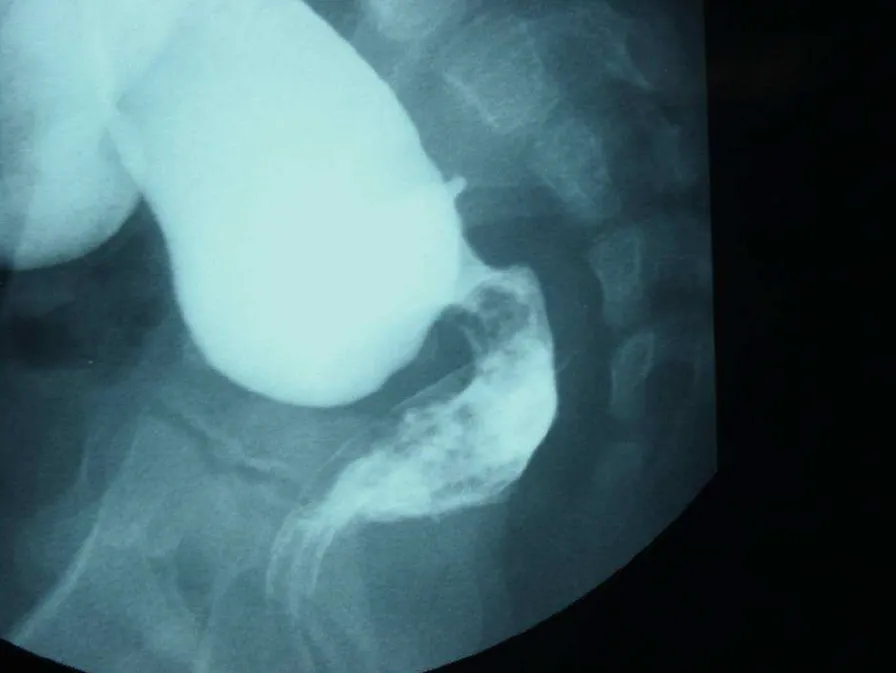

詳解

破題關鍵

這題的解題核心在於辨識下消化道鋇劑攝影中,腸道明顯的「移行區」(transition zone),這是巨結腸症的典型影像特徵,加上新生兒腹脹和胎便延遲排出,診斷就呼之欲出了。

選項拆解

登入查看完整詳解與互動作答